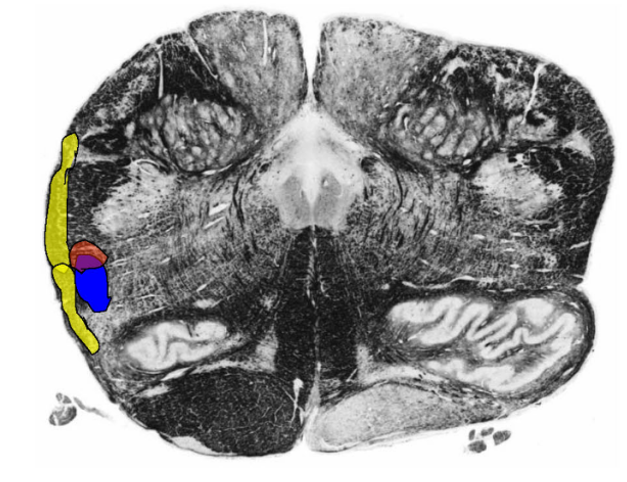

Describe the Spinal Trigeminal Nucleus and Tract

Location

Receives

Pathway of Afferent?

Describe the tuberculum cinereum (or trigeminal tubercle)

Arise from?

Location?

Describe the 3 parts of Spinal Trigeminal Nucleus and Tract

Function

Describe the Somatotopic Organization of the Medulla

Spinal Trigeminal Nucleus and Tract

Location:

within the lateral medulla

Extends caudal pons → upper cervical spinal cord.

Receives:

GSA conveying from Face/External Ear

Pain

Temperature

Crude Touch

Pathway of Trigeminal Afferents:

Enters Brainstem @ level of CNV → Descends in Spinal Trigeminal Tract (located lateral to spinal nucleus) → synapse @ Trigeminal Nucleus along its rostral caudal extent

tuberculum cinereum (or trigeminal tubercle):

Arise from spinal trigeminal nucleus and tract

Located lateral to the cuneate tubercle and tract

3 parts of Spinal Trigeminal Nucleus and Tract

Pars Oralis

Location: rostral pole of hypoglossal N. → caudal end of principal sensory nucleus (Pons))

Function: Tactile input (crude touch)

Pars Interpolaris

Location: level of obex → rostral pole of hypoglossal nucleus)

Function: Dental pain

Pars Caudalis

Location: (C3 → obex)

Function: Pain and temperature

Somatotopic Organization:

V1 synapses ventrally

V2 and V2 synapses progressively more dorsal.

***NOTE: Sensory fibers from the external ear travel in CN VII, IX, and X to synapse in the dorsal most part of the caudal subnucleus (Pars Caudalis)***